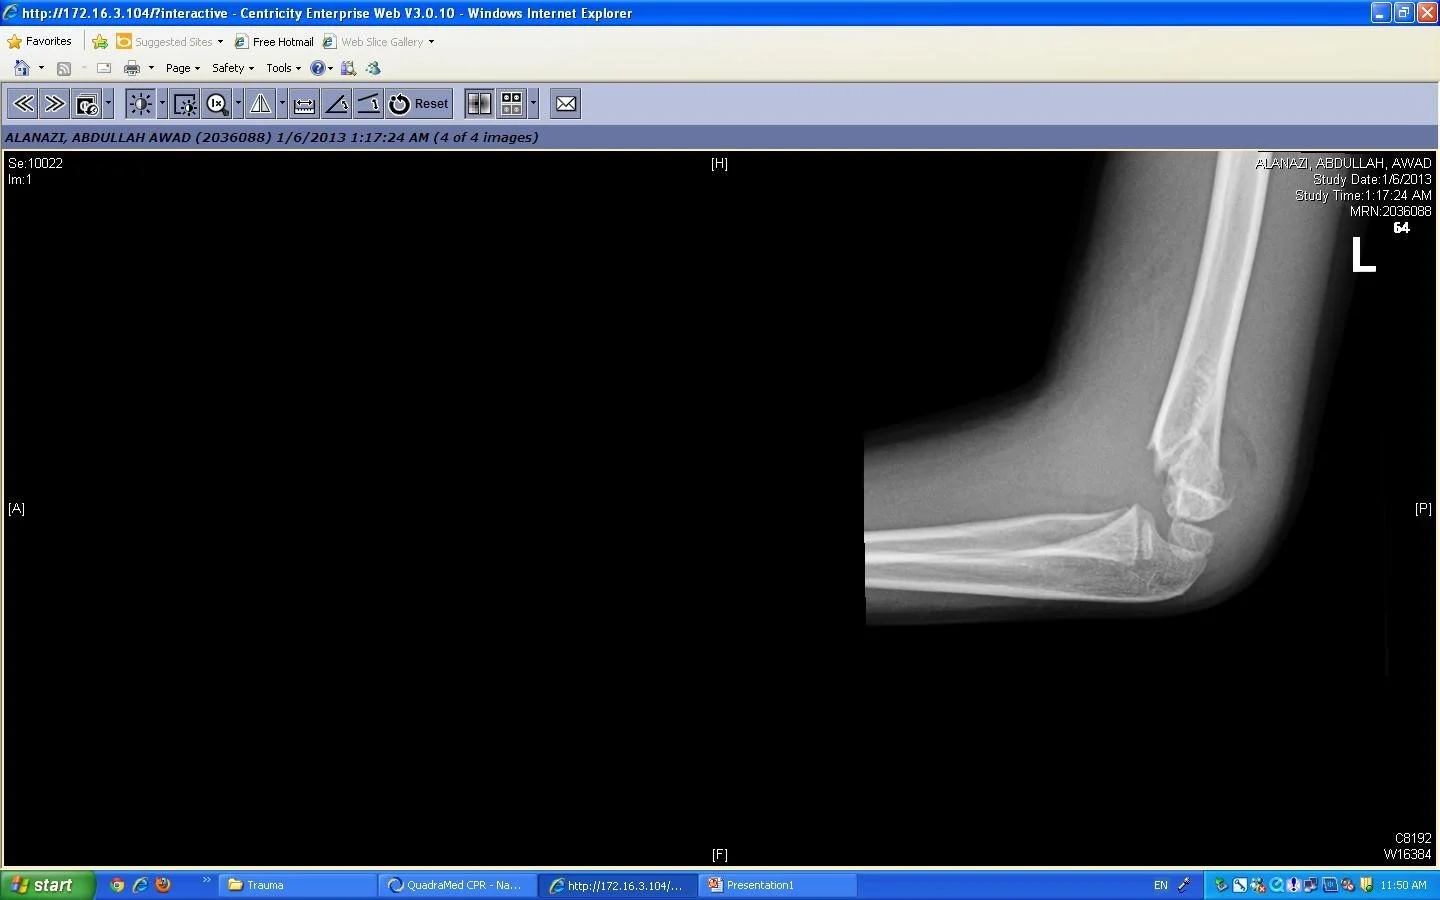

Trauma